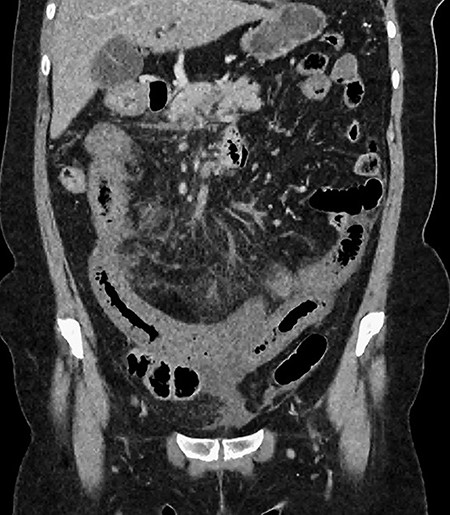

A 61-year-old female presented to a regional hospital with a 3-week history of intermittent diarrhoea, vomiting and generalized abdominal pain. She had a diffusely tender abdomen but was not peritonitic, and was shocked with a heart rate of 110 beats per minute, blood pressure of 89/45 mmHg and was peripherally cool. Her blood tests revealed a lactate of 7.2 mmol/L, which worsened to 7.8 mmol/L during resuscitation with intravenous fluids, and white cell count was 30.9 × 109/L, with an international normalized ratio (INR) of 1.4. She had an acute kidney injury with a creatinine of 119μmol/L and estimated glomerular filtration rate (eGFR) of 43 mL/min/1.73m2. Computed tomography (CT) revealed extensive thickened loops of non-enhancing small bowel with pneumatosis, moderate free fluid and a large splenic infarction. There was extensive thrombosis of the splenic vein and superior mesenteric vein extending into the portal vein to the level of the porta hepatis. Her background history included factor V Leiden and protein S deficiency, for which she had been non-compliant with warfarin during this illness. She had no surgical history (Figs. 1–5).

CT showing complete occlusion of the portal vein at the level of the porta hepatis.